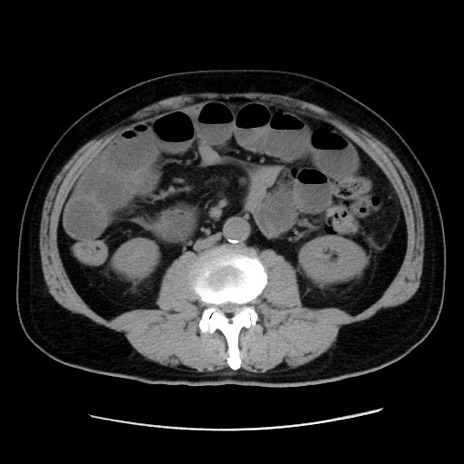

症例16(横断像)

【症例】 70歳代男性

【主訴】 腹痛、嘔吐

【現病歴】 約1ヶ月前より間欠的に腹痛と嘔吐あり、当院消化器内科を受診したところCTで多発する肝臓のLDAを指摘され、精査中であった。以降は消化器症状は安定していたが、2日前より嘔気と腹痛があり、同日より排便・排ガスが消失した。改善認めず、 本日、救急外来を受診した。

【既往歴】 大腸ポリープ切除後。

【身体所見】意識清明・会話良好、BT 36.3℃、BP 127/80mmHg、 P 80bpm、腹部:膨満あり、平坦・軟、上腹部正中および下腹部正中に圧痛あり、反跳痛なし、筋性防御なし。

【データ】WBC 7200、CRP 0.77